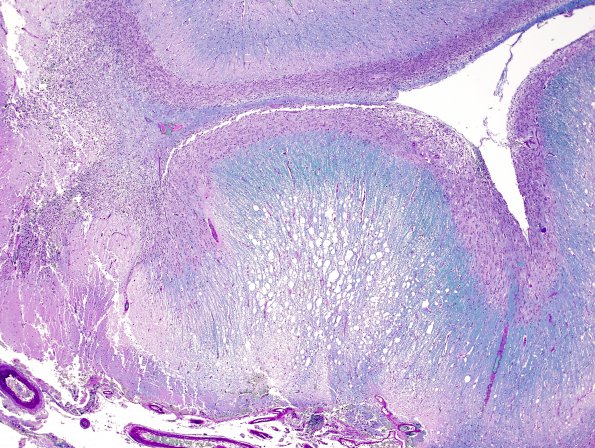

Washington University Experience | NEOPLASMS (NEURONAL) | Lhermitte-Duclos Disease | 2F4 Lhermitte-Duclos (Case 2) B4 LFB-PAS 4.jpg

An LFB-PAS stain for myelin shows an abnormal myelin blue pattern with variable staining of the molecular layer, normally this area has limited myelin staining.